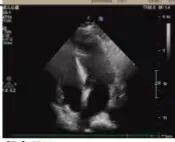

術后超聲

醫學協作創造生命奇跡

術后病理顯示,患者左房腫瘤為良性黏液瘤,完整切除后無需后續治療。經過10天的康復治療,老人順利出院。這一案例中,多學科團隊通過術前風險分層、術中精密協作、術后個體化護理,為高齡復雜心臟疾病患者的救治積累了臨床經驗